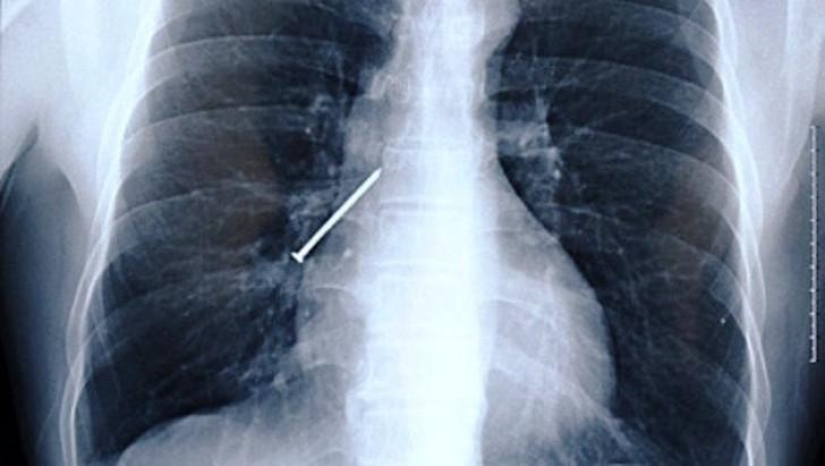

Nail.